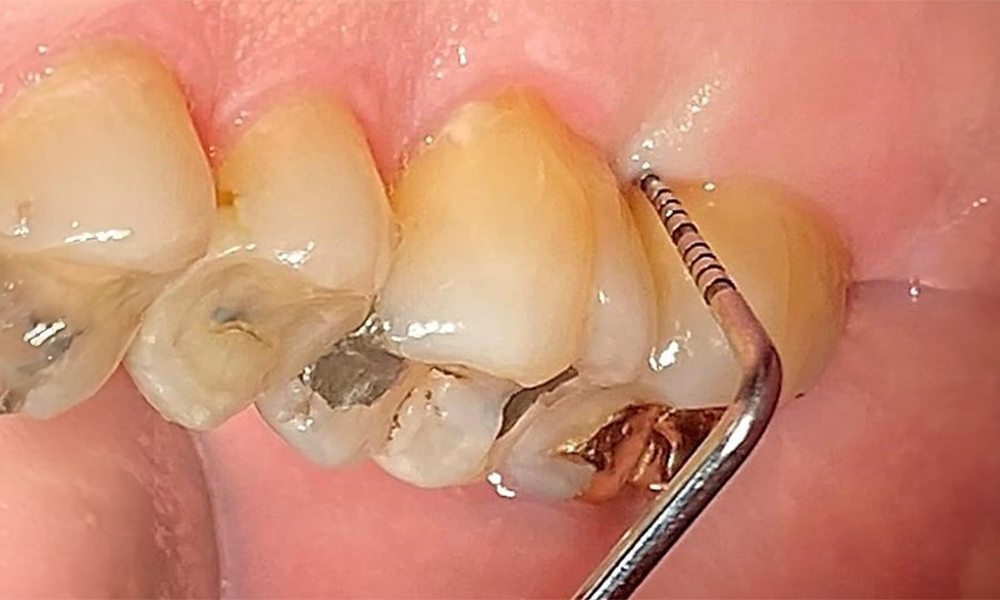

Pacientul prezintă dentiție completă cu 28 de dinți, care include obturații din amalgam și compozit pe molari și premolari. Există un spațiu marginal clinic vizibil la 14. Molarul 27 prezintă un inlay din aur adecvat. Se observă, de asemenea, atriții și abrazii generalizate. (Fig. 2, Fig. 3, Fig. 4, Fig. 5, Fig. 6)

Pacientul prezintă boală parodontală în stadiul II, gradul B (5). Profunzimile clinice de sondare observate, între 1 și 3 mm, se încadrează în limitele fiziologice. Localizat, s-au observat profunzimi de 5 mm, la nivel meziopalatin, atât pe 17, cât și pe 27. Se constată recesiuni generalizate de 1-3 mm, cu pierderi parțiale ale papilelor interdentare (Fig. 2, Fig. 3, Fig. 4)